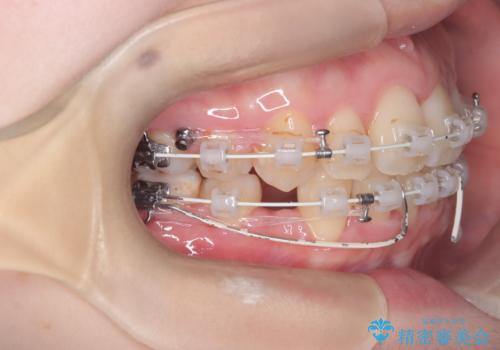

- 「歯のデコボコ、八重歯、口ボコが気になる」を主訴に来院された患者様です。

上下左右4番(4本)の歯を抜歯しワイヤー矯正で治療を行いました。

計4本の抜歯を行い、歯のデコボコと口元がすっきりし、大変ご満足していただけました。